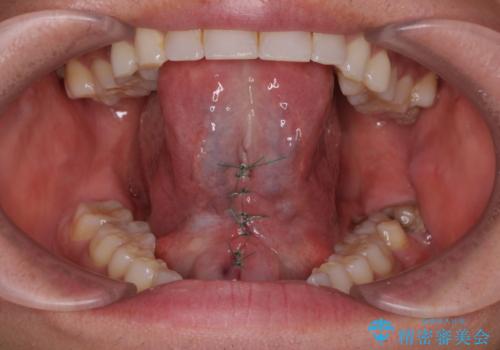

- 滑舌が悪く舌小帯を切りたいとの事で来院。

舌小帯切除術を行いまいした。

1週間後に抜糸をして終了です。